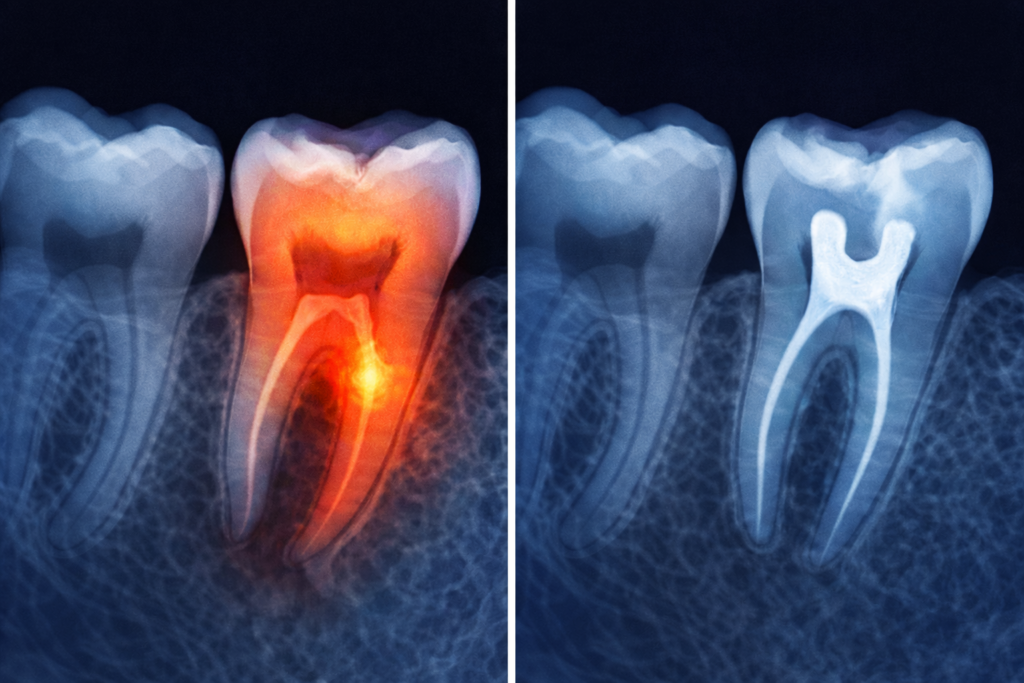

Endodoncia je odborný názov pre zubné ošetrenie, ktoré sa zameriava na vnútro zuba, konkrétne na zubnú dreň. Táto mäkká časť vo vnútri zuba obsahuje nervy, cievy a spojivové tkanivá, ktoré sú dôležité počas vývoja zuba.

Ak sa však dreň zapáli, infikuje alebo nenávratne poškodí, môže sa stať zdrojom silnej bolesti aj vážnejších komplikácií. V takom prípade prichádza na rad endodontické ošetrenie, konkrétne vyberanie nervu zo zuba. Hlavným cieľom zákroku je zachrániť prirodzený zub u pacienta, ktorý by inak bolo nutné už iba vytrhnúť.

Počas zákroku sa odstráni poškodená alebo odumretá dreň, vyčistia sa koreňové kanáliky, vydezinfikujú sa a vyplnia špeciálnym materiálom.

Vyšetrenie: Zákrok začína vyšetrením, počas ktorého zubár posudzuje stav zuba, intenzitu ťažkostí a rozsah poškodenia. Súčasťou diagnostiky býva klinické vyšetrenie, test citlivosti zuba a RTG, ktoré najlepšie ukáže stav koreňov a okolitých tkanív.

Otvorenie zuba: Po príprave nasleduje samotné otvorenie zuba a sprístupnenie koreňových kanálikov. Zubár odstráni poškodenú alebo odumretú dreň a vyčistí zub zvnútra. Cieľom je vyčistiť celý koreňový systém od zápalových a infekčných ložísk.

Hermetické zaplnenie zuba: Keď sú koreňové kanáliky dostatočne vyčistené, vydezinfikované a suché, pristupuje sa k ich hermetickému zaplneniu špeciálnym materiálom. Tento krok zabráni opätovnému prenikaniu baktérií do vnútra zuba.